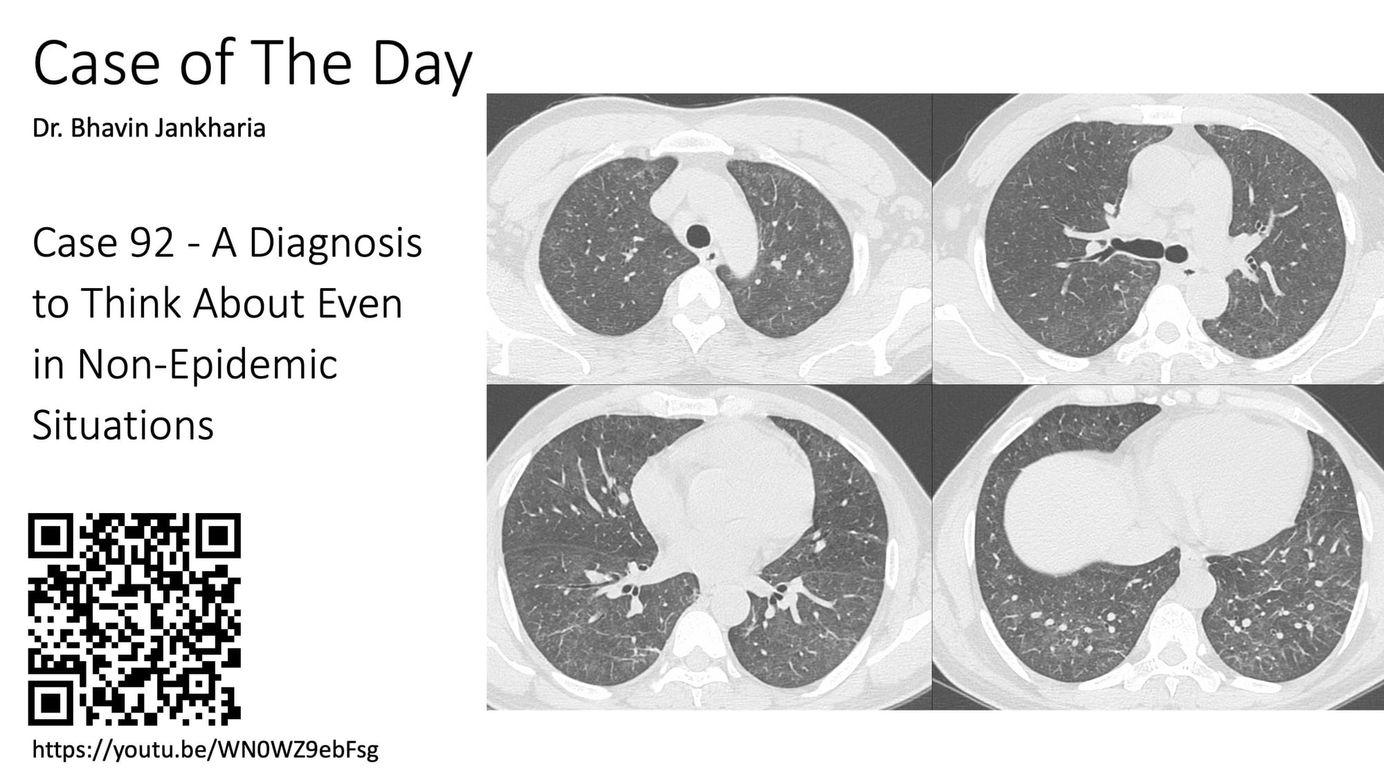

Case of the Day- 092 - 2025 08 27 - A Diagnosis to Think About Even in Non Epidemic Situations Paid Members Public

If this was 1999, it would have been a spot diagnosis.